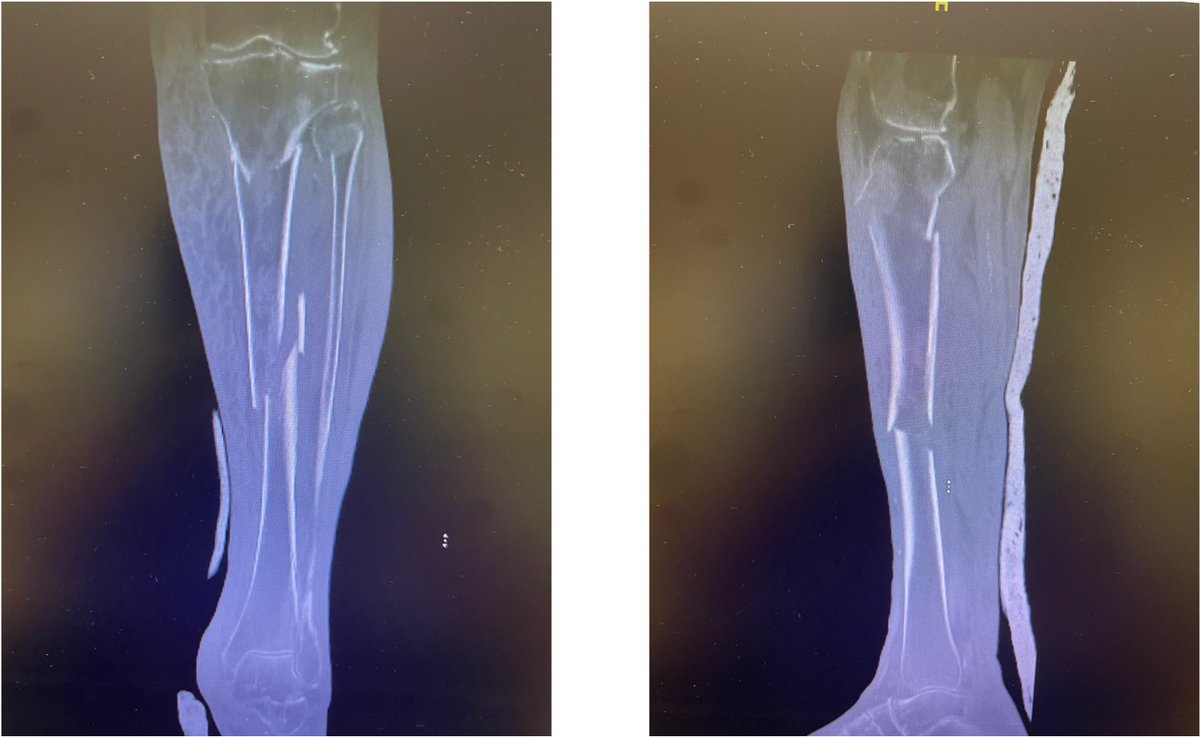

Closed Reduction, Application of Long Leg Cast for Closed Comminuted Diaphyseal Fracture (Middle Third) of the Right Tibia (25/F, Motorcycle accident)

Antonio Tanchuling Jr. M.D. tweet mediaAntonio Tanchuling Jr. M.D. tweet mediaAntonio Tanchuling Jr. M.D. tweet media

@nongtanch I think is better to operate with a nail. Soft tissues control, less ankle and knee stiffness, and avoid rotational secundary displacement, usually in external rotation and early weightbearing

@nongtanch Proximal fibula is also broken and is more expensive for the patient not to work in 4 months, maybe